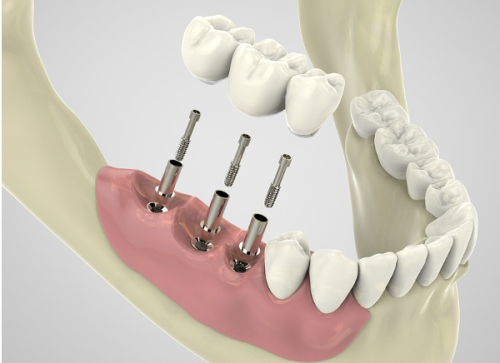

种植牙质量和安装技术的影响

种植牙的质量和安装技术对其使用寿命有着至关重要的影响。高质量的种植体通常采用了精良的材料和工艺,具有良好的生物相容性和稳定性。它们能够更好地与牙槽骨结合,为种植牙提供坚实的基础。而优质的种植牙品牌在研发、生产和质量控制方面都有着严格的标准,能够确保种植体的质量和性能。

专精的安装技术也是确保种植牙成功的关键。经验多的牙科医生能够正确地将种植体植入到合适的位置,确保种植体与牙槽骨的紧密结合。在手术过程中,医生还会根据患者的具体情况,采取相应的措施,减少手术创伤,提高种植成功几率。所以,在选择种植牙时,一定要选择经验多的牙科医生和优质的种植牙品牌,这样才能提高种植成功几率,延长种植牙的使用寿命。